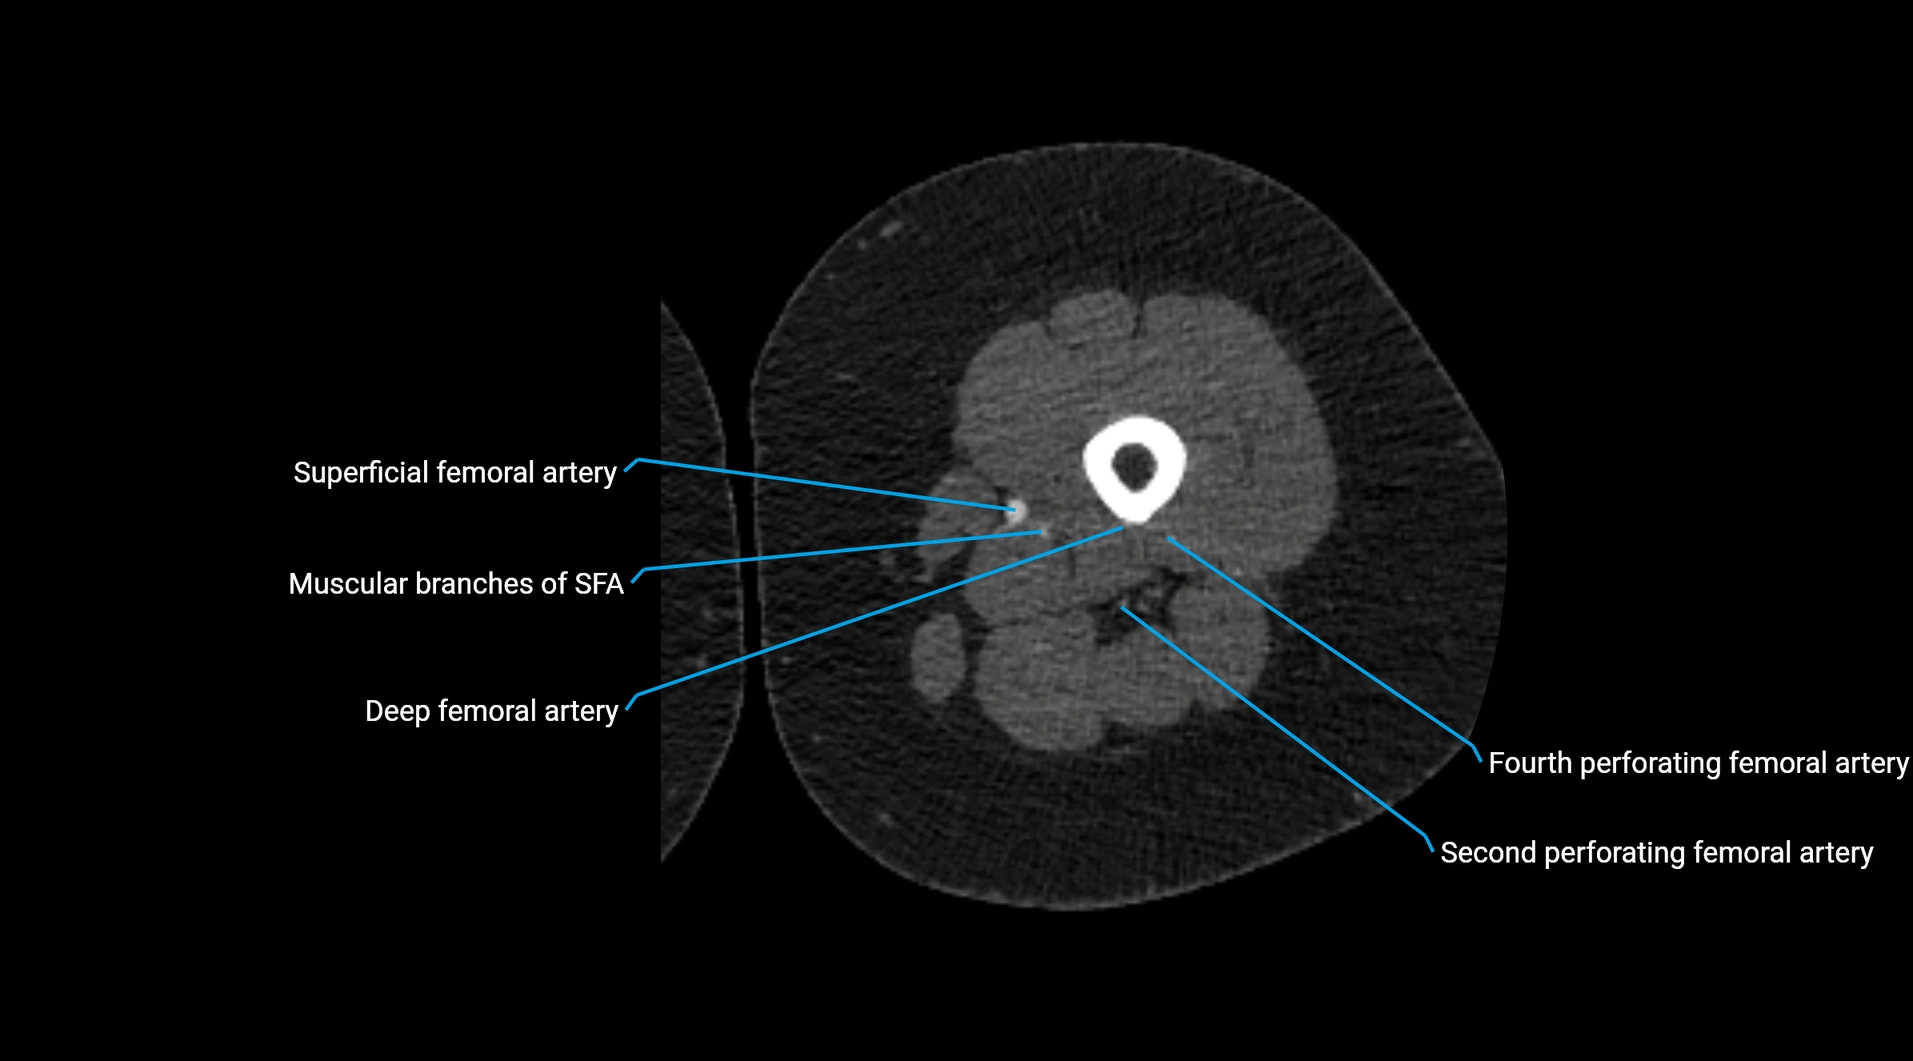

CT images

image